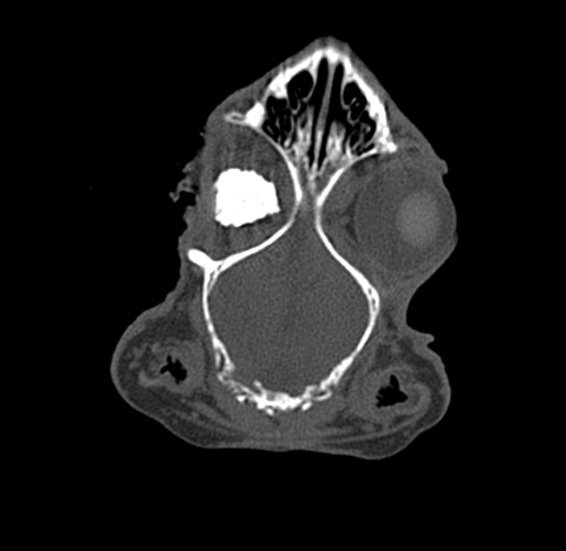

ResultsThe CT analysis performed one month and two months postoperatively has the following values in Hounsfield units, presented in table 2

Maximum density of hydroxyapatite implant at 1 month postoperatively (HU)Maximum density of hydroxyapatite implant at 2 months postoperatively (HU)Normal orbital bone density (HU)Rabbit 1400629989Rabbit 23505891008Rabbit 34305881200Rabbit 4260498970Table 2: density of hydroxyapatite implant measured at CT examination in Hounsfield units

Figure 10: Hydroxyapatite implant – coronal section CT appearance at 1 month postoperatively. Increased bone density is noted inside the implant, but inhomogeneous, with areas of fibrovascular tissue

Discussions CT analysis performed one month postoperatively shows nanostructured hydroxyapatite density values in the scleral sac lower than the bone density of the animal model, but progressively increases at 2 months postoperatively. In terms of density, this is above the density of fibrous tissue but below the bone density of the animal model. In a study published by Froum et al., where a sinus allograft was implanted in humans and allowed to heal, it was demonstrated that a bone volume of about 25% of normal bone volume is sufficient to support a titanium implant8. In the study we found a progressive increase as healing progresses with a maturation of the newly formed tissue from type 2 bone density (300-500 HU) to type 1 bone density (over 500 HU). Histopathological analysis shows bone tissue formation inside the implant, the presence of fibrovascular tissue but also inflammatory cells. Also, the large number of osteoclasts is a marker of the degradation of nanostructured hydroxyapatite in the local production of new bone. Considering the existence of an extensive infectious process in one of the subjects that required the administration of general and local antibiotics for a longer period, the presence of inflammatory tissue rich in polymorphonuclear cells and lymphocytes is a valuable marker of the existence of this complication. However, it is known that inflammatory tissue transforms over time, after the resolution of the infection, into fibrous, scar tissue, which for this type of implant does not constitute a disadvantage, it can only be considered the possibility that the fibrosis process inside the implant may last longer. Conclusions: The progressive increase in the formation of fibrous tissue and new bone as healing progresses with a maturation of the newly formed tissue from type 2 bone tissue (300-500 HU) to type 1 bone tissue (over 500 HU) argues for the possibility of adapting a rapid dowel and screw to the animal model. In addition, histological analysis of the newly formed tissue inside the scleral sac reveals the rapid formation of bone and osteoid material alongside fibrovascular tissue, which is an important premise in promoting nanostructured hydroxyapatite materials in the prosthesis of the anophthalmic cavity. Moreover, the presence of CD31 and CD34 positive cells argues for rapid angiogenesis and fibrogenesis.